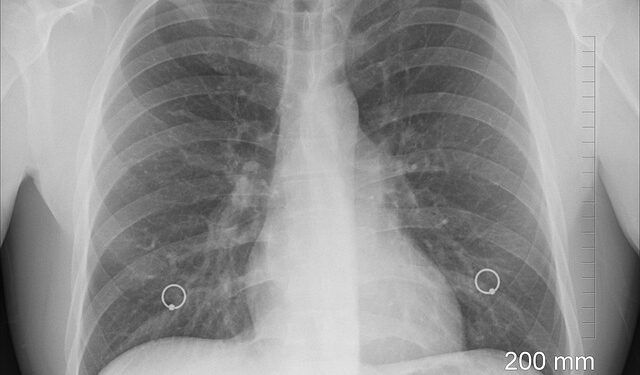

Pneumonia este o boală respiratorie acută care afectează plămânii şi care este produsă de agenţi infecţioşi. Gripa, virusul sinciţial respirator şi bacteriile pneumococice sunt cauze frecvente ale pneumoniei, care este determinată în general de microorganisme precum bacterii, viruşi şi fungi. Simptomele cele mai frecvente ale pneumoniei sunt: febră, frisoane, tuse cu producere de spută, dureri toracice, transpiraţie excesivă, dificultatea în respiraţie (dispnee), starea de oboseală şi scăderea poftei de mâncare.